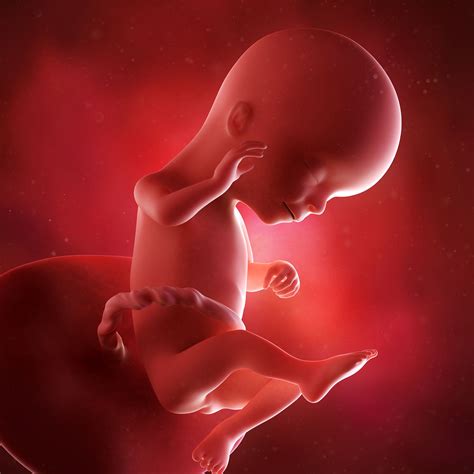

• Baby's Size and Development: At 16 weeks, your baby is about the size of an avocado, measuring approximately 4.5 to 5.4 inches (11.4 to 13.7 centimeters) in length and weighing around 3.5 ounces (100 grams). The baby's body is becoming more proportional, and the head-to-body ratio is decreasing.

• Movement: Although you might not feel it yet, your baby is becoming more active. The baby can make facial expressions, suck their thumb, and even practice swallowing amniotic fluid.